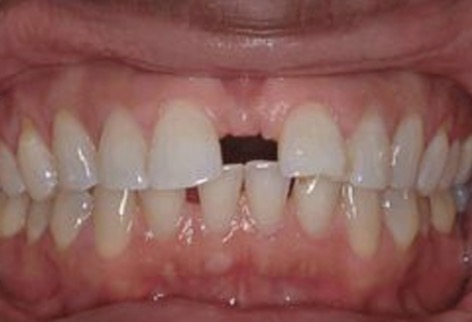

What is this condition?

Diastema

-can occur from strong frenum attachment or genetics